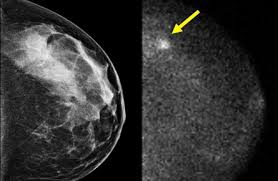

Any area that does not look like normal tissue is a possible cause for concern. Magnetic resonance imaging (mri) of the breast — or breast mri — is a test used to detect breast cancer and other abnormalities in the breast. Breast cancer and some noncancerous (benign) breast conditions can appear white on a mammogram. Microcalcifications, which look like white specks on a mammogram. What does an abnormal mammogram look like? Breast mri images are combined, using a computer, to create detailed pictures. Mammograms may show suspicious areas of the breast, white spots, and microcalcifications. In addition to mammograms, ultrasound and mri may also be used to take a closer look at changes in the breast. Tumors are likely to be smaller when doctors detect them early, which can. This type of cancer also changes the appearance of your breasts. A lump or tumor will show up as a focused white area on a mammogram. This appears most commonly as streaking, known as linear enhancement. There are few risks associated with mammography.

Microcalcifications, which look like white specks on a mammogram. They will look carefully at the mammogram to interpret the results. Tumor size is an important factor in breast cancer staging, and it can affect a person's treatment options and outlook. Breast mri images are combined, using a computer, to create detailed pictures. Breast cancer can appear as a spiculated mass, cluster of tiny calcifications, smoothly marginated mass, area of subtle distortion or be invisible on. Magnetic resonance imaging (mri) of the breast — or breast mri — is a test used to detect breast cancer and other abnormalities in the breast. Calcifications are calcium deposits within the breast tissue and they look like small white spots. A breast cancer tumor on a mammogram is often irregular with edges that don't look smooth. A 3d mammogram is used to look for breast cancer in people who have no signs or symptoms. A rash isn't the only visual symptom of inflammatory breast cancer. A mammogram can show breast changes such as calcifications, masses, or other symptoms that might be cancer. This appears most commonly as streaking, known as linear enhancement. What does cancer look like on a mammogram?

This appears most commonly as streaking, known as linear enhancement. As with all abnormalities seen on breast imaging, the diagnosis of dcis requires a sample of tissue or biopsy. What does breast cancer look like on a mammogram? Calcifications are calcium deposits within the breast tissue and they look like small white spots. Breast cancer can appear as a spiculated mass, cluster of tiny calcifications, smoothly marginated mass, area of subtle distortion or be invisible on.